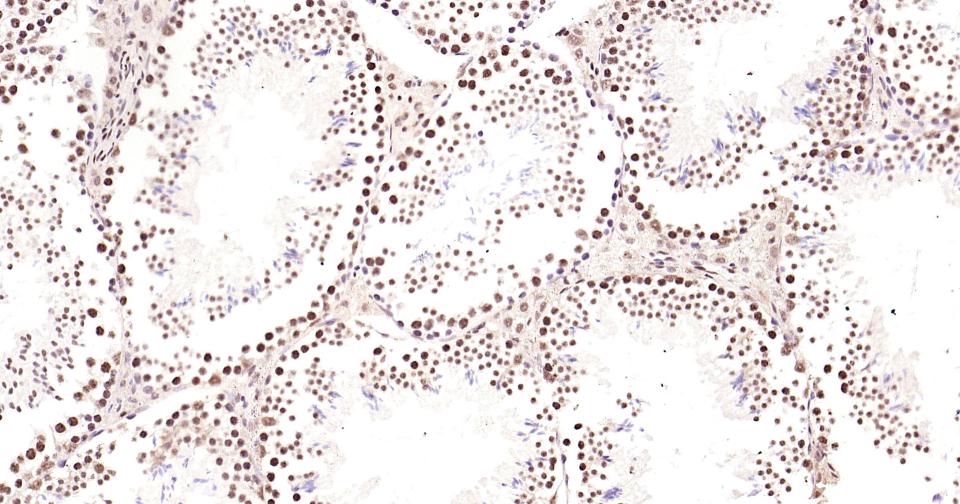

Paraformaldehyde-fixed, paraffin embedded Mouse Testicles; Antigen retrieval by boiling in sodium citrate buffer (pH6.0) for 15 min; Antibody incubation with Phospho-CREB-1 (Ser133) Monoclonal Antibody, Unconjugated(bsm-61105R) at 1:200 overnight at 4°C, followed by conjugation to the bs-0295G-HRP and DAB (C-0010) staining and DAB (C-0010) staining.